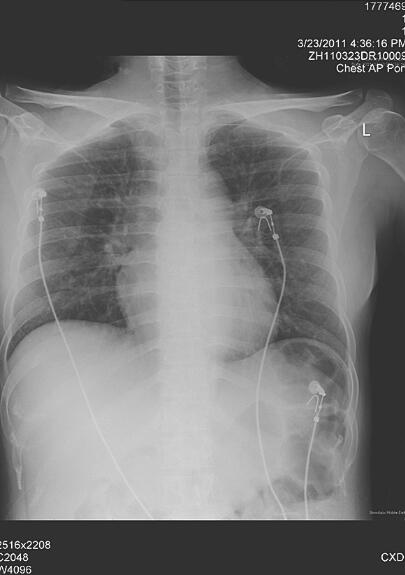

诊治经过:患者入院后3次痰找结核分枝杆菌阴性,PPD阴性,抗结核抗体阴性,ANA 1∶80,ANCA阴性,予左氧氟沙星和头孢呋辛抗感染,同时予胰岛素控制血糖,积极补液降酮体,每天入量5000ml左右(静脉输液1000ml,口服补液4000ml左右),尿量4000ml左右,1天后复查血气分析示pH 7.36,PO2 99mmHg,PCO2 26mmHg,HCO3− 14.7mmol/L,SaO2 97%,尿常规酮体阴性,胸片(图3)示双肺渗出性病变,较前吸收,5天后复查超声心动图示左心室壁运动减低,三尖瓣轻度反流,LVEF 43%。患者体温正常,血象正常,呼吸困难逐渐消失,复查胸片(图4)基本正常。9天后复查BNP 567.5pg/ml。出院后4个月随访,患者日常活动下无胸闷、气短,复查超声心动图示心内结构正常,舒张功能减退,LVEF 54%。

图4 入院后第6天复查胸片基本正常